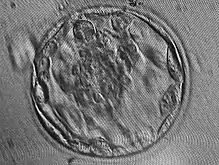

تعد الكيسَةُ الأُرَيمِيَّة (blastocyst) تكوينًا تشكَّل في وقتٍ مبكرٍ لتطور الفقاريات.[1][2][3] ويسبقها التوتية (morula). تحتوي على كتلة الخلايا الداخلية (ICM) أو الأرومَةٌ المُضْغِيَّةٌ (embryoblast)، والتي تُشكِّل الجنين بعد ذلك، والطبقة الخارجية من الخلايا، أو الأَرومَةُ الغاذِيَة (trophoblast), التي تُشكِّل المشيمة (placenta) فيما بعد. تُعرَف الأَرومَةُ الغاذِيَة التي تحيط بكتلة الخلايا الداخلية وتجويف الكيسَةُ الأُرَيمِيَّة المملوء بالسائل باسم جوف الأريمة (blastocoele) أو التجويف الكيسَي الأُرَيمِي. تضم الكيسَةُ الأُرَيمِيَّة للإنسان 70-100 خلية.

يبدأ تكوين الكيسَةُ الأُرَيمِيَّة في اليوم الخامس بعد الإخصاب عند الإنسان، عندما ينفتح جوف الأريمة في التوتية، وهي عملية تُعرَف بالتفقيس (hatching).[بحاجة لمصدر]